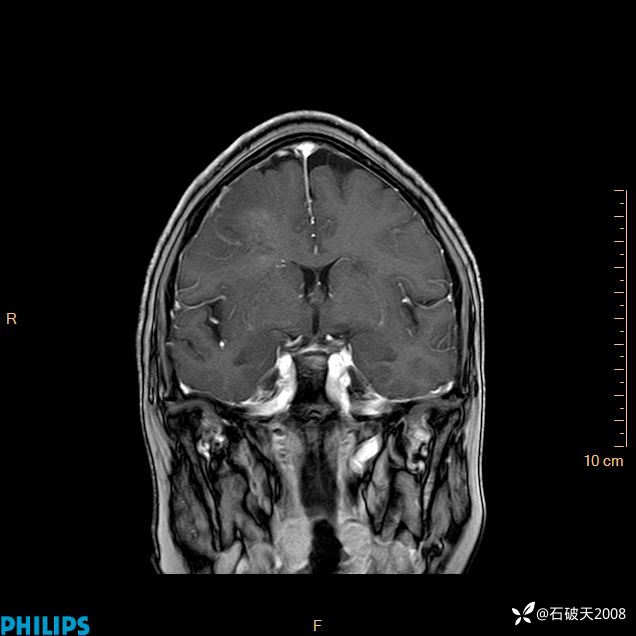

2024.2.21MR

增强冠状位